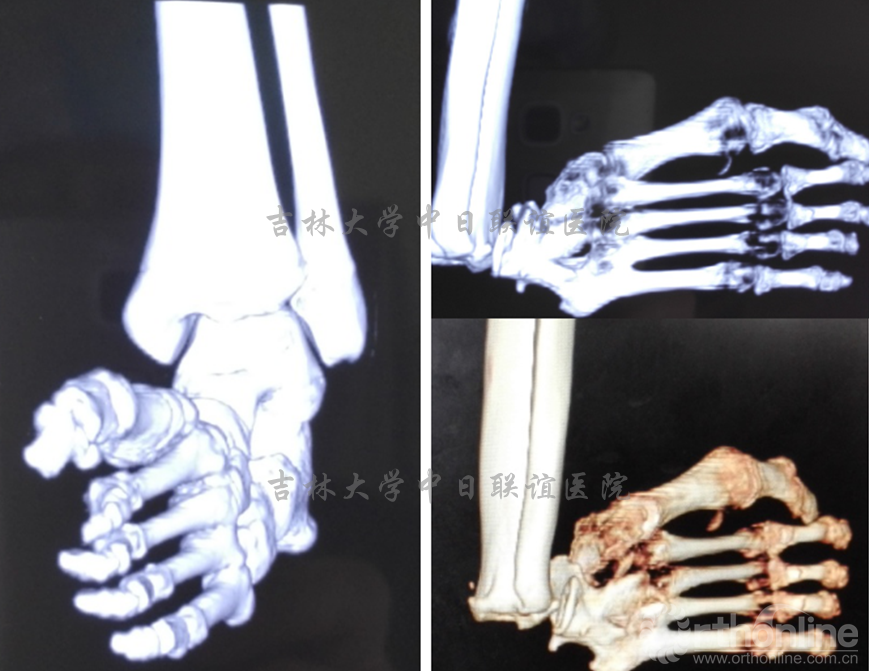

脊柱短缩截骨术后1年后行双足畸形矫形术:术后1年,患者双下肢感觉、肌力明显好转。一期右足行皮肤软组织松解覆盖创面3月后二期行矫形手术治疗。

影像学检查及外相: